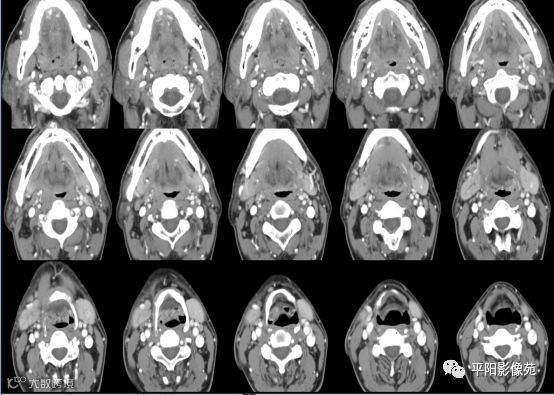

患者 男 47岁

主诉: 发现右侧颌下肿物一年余。

现病史:患者于一年前因全身发烧,全身抗感染对症治疗大约一周后,发烧症状消失,后出现右侧颌下区肿胀,约鸡蛋大小,舌下区也出现轻度肿胀,挤压颌下区舌下区可出现唾液分泌,无疼痛、皮肤发红等不适症状,出现进食时右侧颌下区肿胀史,口服阿莫西林效果不佳,为行进一步治疗,来我院门诊以“右侧颌下区肿物”收住入院。入院以来精神饮食正常,大小便正常,近期体重无明显改变。

专科情况:右侧颌下区稍肿胀,皮肤不发红,局部可触及约5*4*3cm大小椭圆形肿物,活动性好,表面呈不规则状,无明显触痛,挤压口底无明显肿胀,导管口通畅,挤压导管口有少量唾液流出。

双侧颌下腺、腮腺对称,形态完整,右侧颌下腺强化程度较左侧略低,其内涎腺管增粗,周围脂肪间隙清晰,邻近骨质未见异常,右侧涎腺走行区可见结节样致密影,较大者大小约0.5cm,双侧颌下软组织对称,未见异常密度,所扫范围颈部未见明显肿大淋巴结。

考虑右侧涎腺管结石。

右侧颌下腺强化程度较左侧略低,涎腺管扩张,考虑炎性改变,请结合临床。